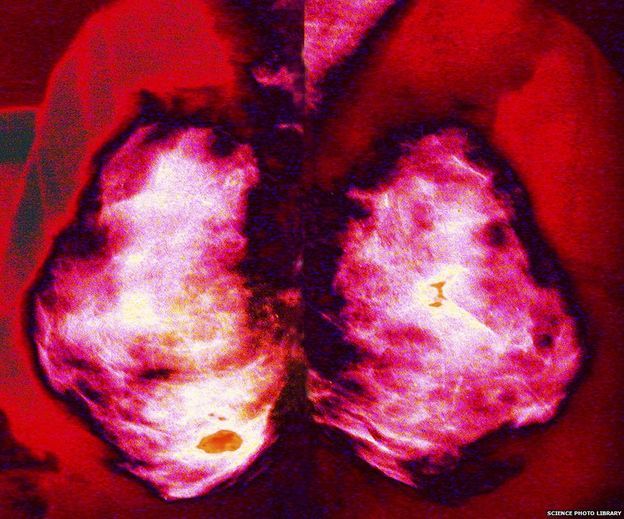

O câncer é a doença que apresenta o segundo maior risco de morte para as pessoas, mas os exames para detectar a doença geram polêmica. Muitos críticos afirmam que estes exames podem prejudicar mais do que ajudar.

Um exemplo é o exame para detectar câncer de mama, que está disponível na rede pública de saúde da Grã-Bretanha para todas as mulheres entre 50 e 70 anos de idade – e este limite de idade deve aumentar para 73 em 2016.

Um relatório feito no país, chamado de Marmot Report, analisou as provas de eficácia deste programa e concluiu que o exame salvou 1,4 mil vidas por ano.

O Nordic Cochrane Centre, em Copenhague, na Dinamarca, é um centro respeitado de colaboração internacional entre cientistas e instituições. E discorda do relatório.

Segundo o centro dinamarquês, pelo fato de termos melhores tratamentos para câncer de mama, a defesa da mamografia ficou prejudicada e, estudos recentes “mostram pouca ou nenhuma redução da incidência de cânceres avançados com o exame”.